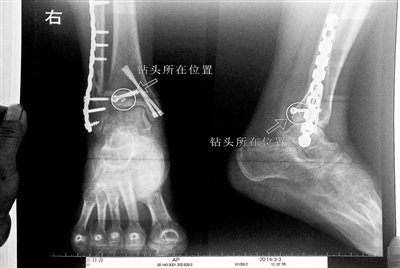

15、北京:女子做完手術鉆頭被落骨頭里?院方稱危害不大

看著X光片中自己腿內的異物,胡女士就感到莫名的擔憂。胡女士于2013年3月在北京市豐臺區右安門醫院進行了一次骨折手術,術后醫生才發現手術時用來打眼用的鉆頭不慎遺留在了胡女士的骨頭中,并且無法取出。